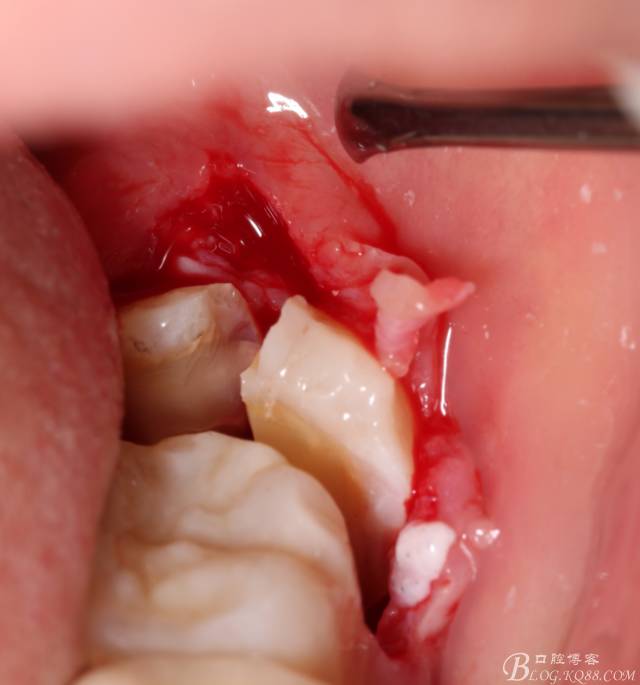

取出阻力部分冠

640 (13).jpg

在取出阻力冠后,嘗試性看能取出全部的牙體不,就是取不出也能整體撬動(dòng)牙根。